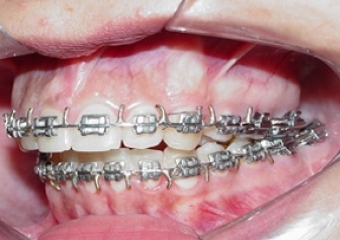

Mordida após a remoção do aparelho